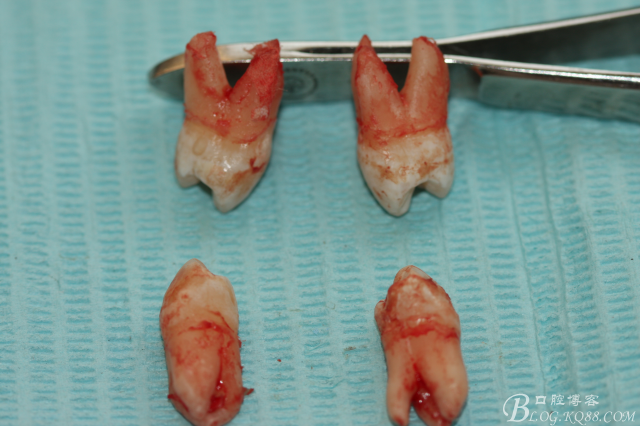

患者:江某某、男、14歲。因正畸治療需要拔除上下頜四顆第一前磨牙。按醫(yī)囑,局麻下拔除四顆第一前磨牙。牙齒拔除后發(fā)現(xiàn)四顆牙齒均為三個(gè)根,頰側(cè)兩根,腭側(cè)一個(gè)根。上頜第一前磨牙偶見三根。下頜第一前磨牙左右兩側(cè)均為三根,實(shí)屬罕見。發(fā)圖片,與同仁共勉。

手術(shù)圖片:

5.上頜離體第一前磨牙牙根形態(tài)

6.下頜離體第一前磨牙牙根形態(tài)

7.四顆離體上下頜第一前磨牙牙根形態(tài)